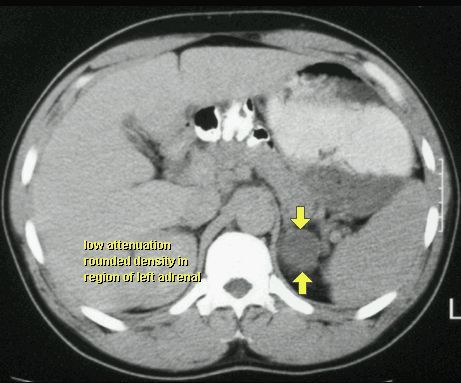

TK

GRUCZOLAK NADNERCZA